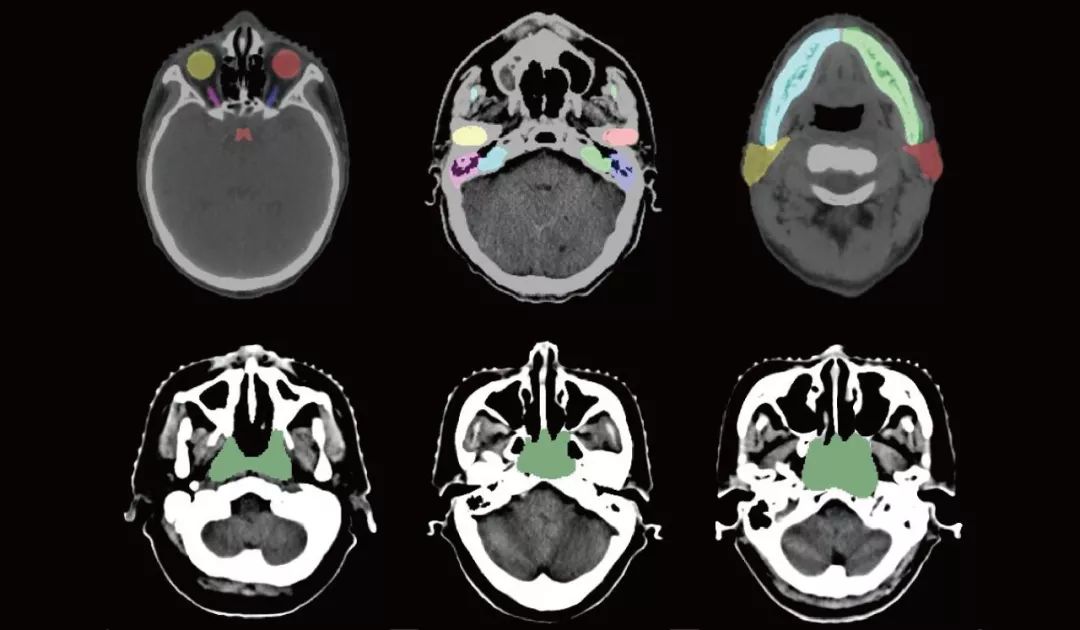

但是,业内还普遍缺乏标准化高质量的训练数据,此次MICCAI 2019放疗规划自动结构勾画国际挑战赛,就将公布大量具有专家标注的CT数据,用于此次“头颈部危及器官(OAR)分割”、“胸部危及器官(OAR)分割”、“鼻咽癌放疗靶区(GTV)分割”和“肺癌放疗靶区(GTV)分割”四项挑战任务。

这些CT数据包含鼻咽癌与肺癌两种癌症数据,且本次数据集规模比以往所有公开数据集规模都大,包含了50位鼻咽癌患者的CT数据及相应的1100个危及器官和放疗靶区GTV的标注,50位肺癌患者的CT数据及相应的300个危及器官和放疗靶区GTV的标注,这些数据集的释放,将极大地推动CT图像中危及器官和靶区勾画研究的进展。